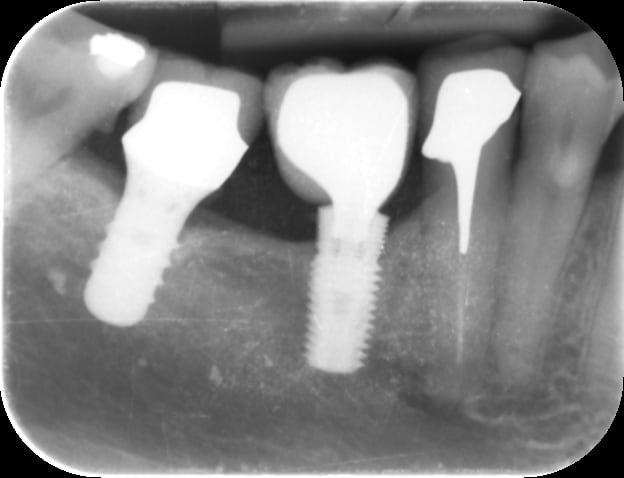

Bonjour, renseignements pris l 'implant 46 serait un medical production ICC 45 10 avec une vis VFIC ZI . Je dois refaire la couronne cassée. Quelqu'un peut me dire si c'est une connexion répandue que je pourrais trouver chez DESS par exemple ? merci

Oui, connexion astra lilac